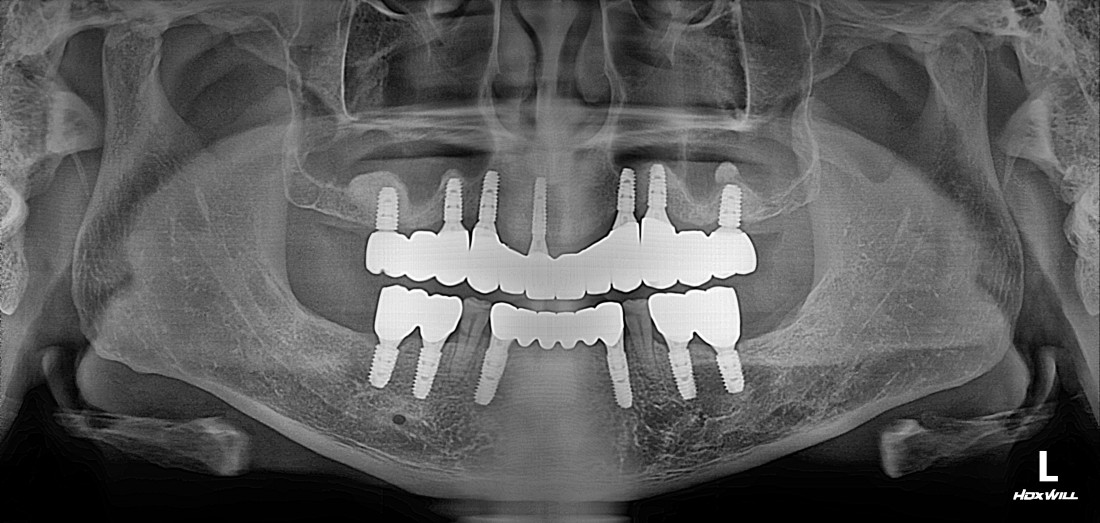

수완동 임플란트 치과는

수 백개의 임플란트 전/후 케이스 사진을

홈페이지에 공유하고 있습니다.

전체 임플란트부터

신경쓰이는 앞니 임플란트,

20대 / 30대 임플란트 케이스부터

80대가 넘는 분들의 케이스까지

정말 다양한 모든 케이스를 보유하고 있습니다.

다양한 각도의 임플란트 식립 전/후 사진으로

실력에 자신있는

수완동 임플란트 치과입니다.